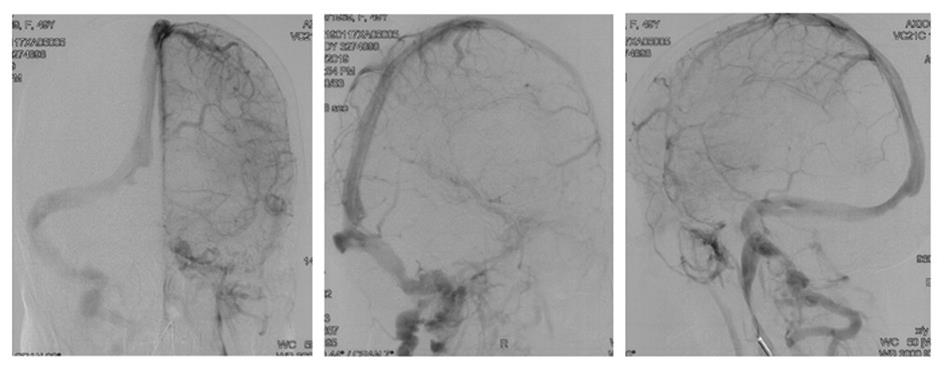

• 挽救性支架植入对取栓困难的脑动脉栓塞开通效果

2022, 47(7):779-783. DOI: 10.13406/j.cnki.cyxb.003067

摘要:目的 探究急性脑栓塞取栓失败和神经介入术中发生医源性脑动脉栓塞后补救性支架植入术的开通效果。方法 回顾性分析2020年1月至2021年11月上海交通大学医学院附属第九人民医院6例脑栓塞取栓失败和4例医源性颅内中远端动脉栓塞、接受补救性支架植入术的患者临床信息,总结患者术后血管开通情况、术后24 h 支架内血流通畅情况、出血转化和预后等情况。结果 6例急性脑栓塞取栓失败,补救性支架植入后闭塞血管全部开通(modified thrombosis in cerebral infarction score,mTICI 2b~3),术后3例出血转化(1例PH2型,2例HI2型),术后24 h支架内血流通畅5例(83%),1例未行血管造影复查;3例患者住院期间死亡。4例医源性中远端动脉闭塞中,1例为原发病为椎基底动脉高度狭窄,支架置入术中发生右侧小脑前下动脉闭塞,补救性支架置入后完全开通,术后24 h复查所有支架通畅,无脑出血,3个月预后良好,改良Rankin量表(modified Rankin score,mRS)评分1分;3例原发病为大脑中动脉栓塞,取栓术中出现同侧大脑前动脉分支闭塞,补救性支架植入后完全开通,其中1例术后24 h头颅计算机体层血管成像(computed tomography angiography,CTA)可见支架通畅,合并片状出血转化(HI2型),2例因为病重未行血管复查。结论 补救性支架植入可以快速开通取栓失败以及医源性中远端动脉的栓塞,但是疗效和安全性需进一步研究。